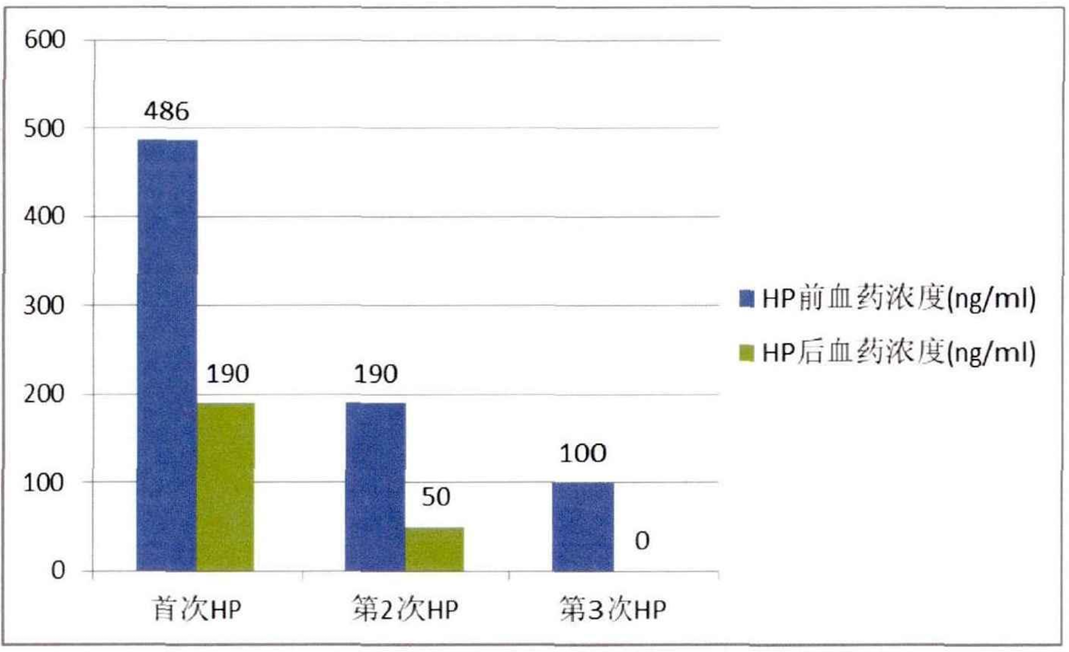

從理論上講,當毒物在血液中達到峰值濃度時,吸附效果最佳。多數情況下,由于無法明確接觸毒物的種類和劑量,難以預測峰值。普遍認為,血液灌流在患者暴露于毒物后6小時內最有效,此時血液中大多數藥物或毒物的濃度較高,毒物擴散到周圍組織較少。為了防止治療后周圍組織蓄積的毒物再次分布入血造成濃度反彈,需要早期、反復血液灌流治療。[4]

圖2 急性有機磷中毒患者血液灌流不同次數后的血藥濃度